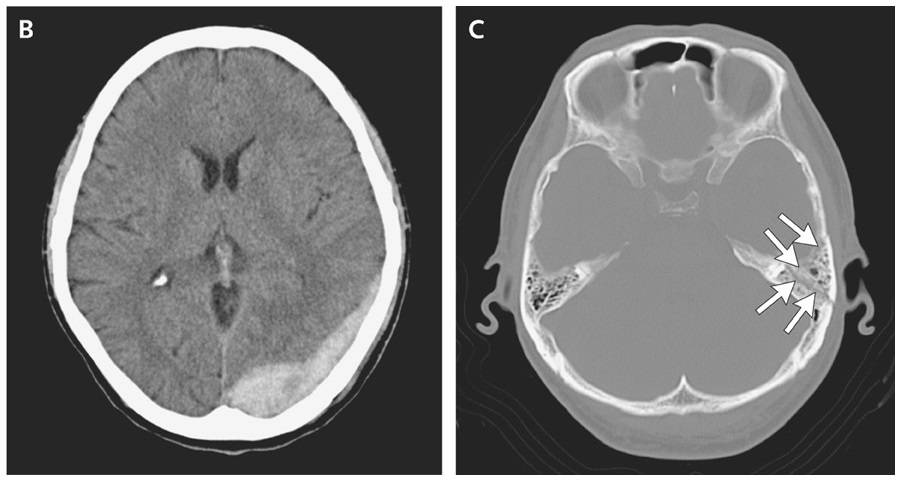

Computed tomography revealed an acute epidural hematoma (Panel B), accompanied by a left temporal bone fracture (Panel C, arrows).